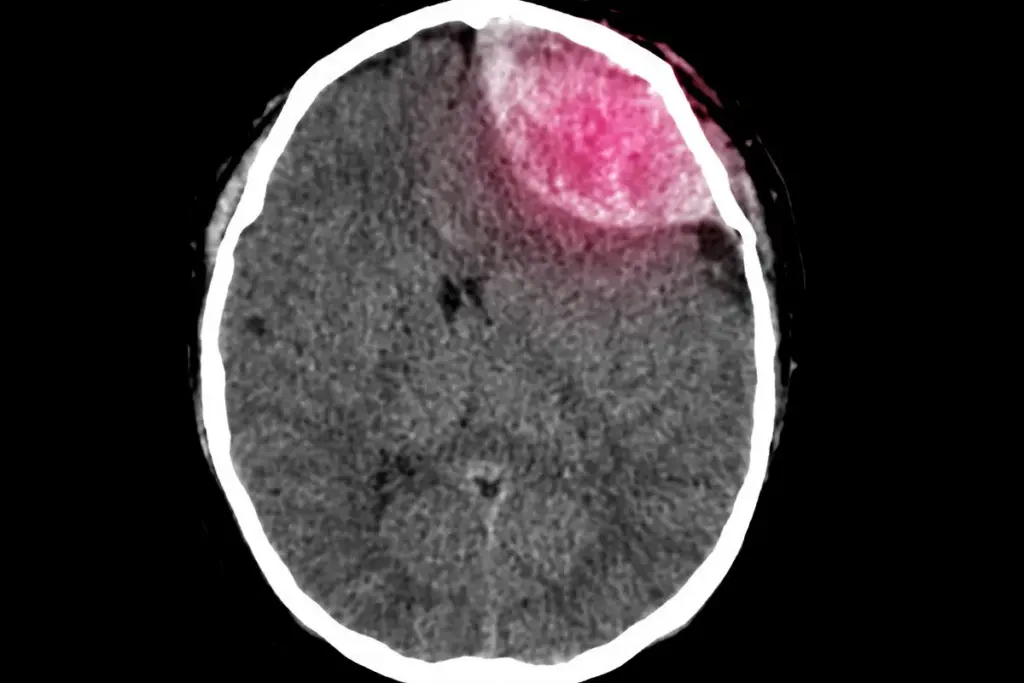

Brain surgery is a complex medical procedure. It treats serious conditions like tumors, blood clots, and epilepsy. The risks and complexity make it a daunting choice for many.

There are many types of brain surgery, each with its own risks. Some are considered major surgeries because they’re very complex. These surgeries involve critical brain areas or require removing a lot of brain tissue.

Why Brain Surgery Carries Inherent Risks

Brain surgery is risky because of the brain’s delicate nature. The brain controls many body functions. Damage can lead to serious problems, like speech or vision issues.

Some risks of brain surgery include:

- Bleeding or hemorrhage

- Infection

- Blood clots

- Stroke or cerebral vasospasm

- Damage to surrounding brain tissue

These risks are made worse by the complexity of neurosurgical procedures. These surgeries often involve navigating through delicate brain structures.